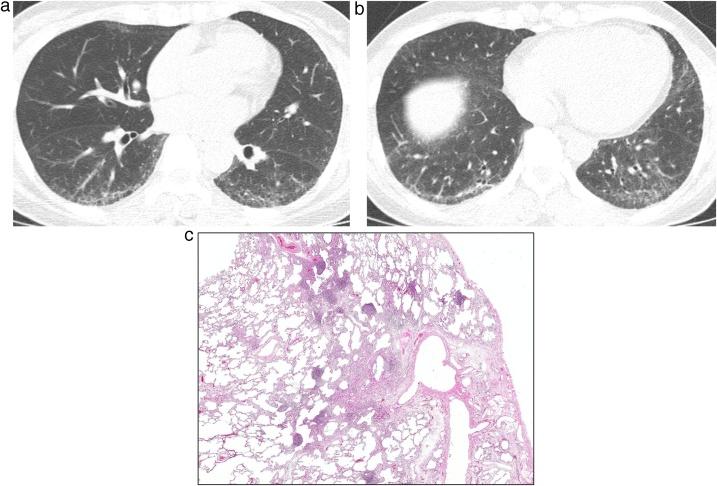

Interstitial lung abnormality (ILA) and nonspecific interstitial pneumonia (NSIP).

This review article aims to address mysteries existing between Interstitial Lung Abnormality (ILA) and Nonspecific Interstitial Pneumonia (NSIP). The concept and definition of ILA are based upon CT scans from multiple large-scale cohort studies, whereas the concept and definition of NSIP originally derived from pathology with evolution to multi-disciplinary diagnosis. NSIP is the diagnosis as Interstitial Lung Disease (ILD) with clinical significance, whereas only a part of subjects with ILA have clinically significant ILD. Eventually, both ILA and NSIP must be understood in the context of chronic fibrosing ILD and progressive ILD, which remains to be further investigated.